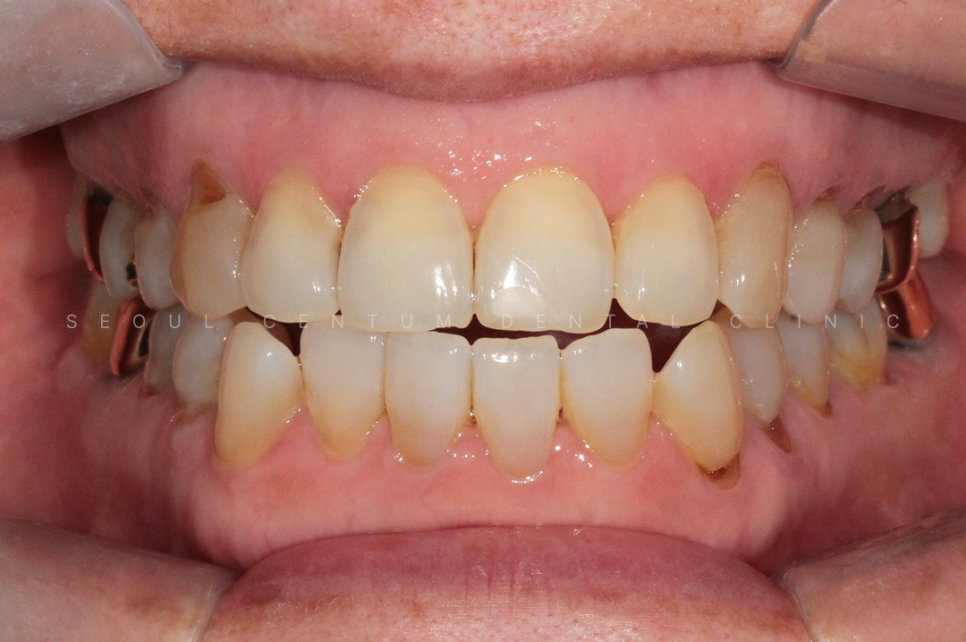

아래 사진은 실제 서울센텀치과에

치경부마모증이 뭔지 모르는 상태로

내원하셔서 치료를 하게 된 케이스인데요.

60대 여성으로 동네에 치과에 스케일링을

오랫만에 하러 갔다가

치아가 파였다는 말을 듣고

거울을 보고나니 치아가 보기 싫어져서

라는 이유로 내원을 하셨어요.

실제 육안으로 봤을 때도 크게

치경부마모증이 진행된 부분이 많았고

당일에 바로 진행을 하게 되었습니다.

크게 진행이 된 8개의 치아를 진행하기로 했고

강도가 강한 레진으로 진행해 오래

유지를 잘 해보시기로 이야기가 되어

레진으로 진행을 했습니다.